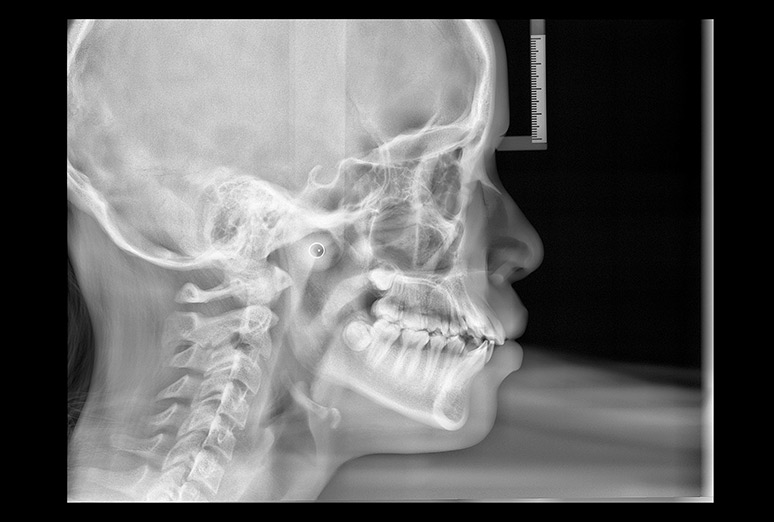

Teleradiografía

Radiografía Lateral de Cráneo, permite hacer todo tipo de mediciones faciales.

Análisis Cefalométrico

Análisis facial con mediciones de puntos craneometricos.